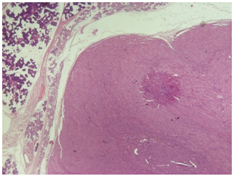

Pathological examination of the tissue sections revealed a 1,5 cm circumscribed neoplasm with tan color partially encapsulated, covered by healthy parotid tissue. A lymphe node 2,1 cm was also present but had non specific reactive changes. The neoplasm had a nested pattern of growth suggesting an oncocytoma. It composed of cells with vesicular nuclei, with prominent nucleoli and abundant granular acidophilic cytoplasm. (Figure 1) (Figure 2). Enhanced mitosis, cytological atypia, moderate nuclear pleomorphism and necrosis were noted. Focally an abnormal circumference with connective tissue and fibrous elements was also present suggesting that this neoplasm has agressive histological features with malignant potential. Immunohistological staining pattern showed that the neoplastic cells had a Ki67 positive at 8% (Figure 3), positve for ker 8/18 (Figure 4), positive-negative for p63 while were negative for ker 14, SMA, CEA, TTF-1, CD31, calcitonin, EMA, GFAP, and S100 staining.

Figure 1 Ex 2.5: A circumscribed neoplasm covered by healthy tissue.